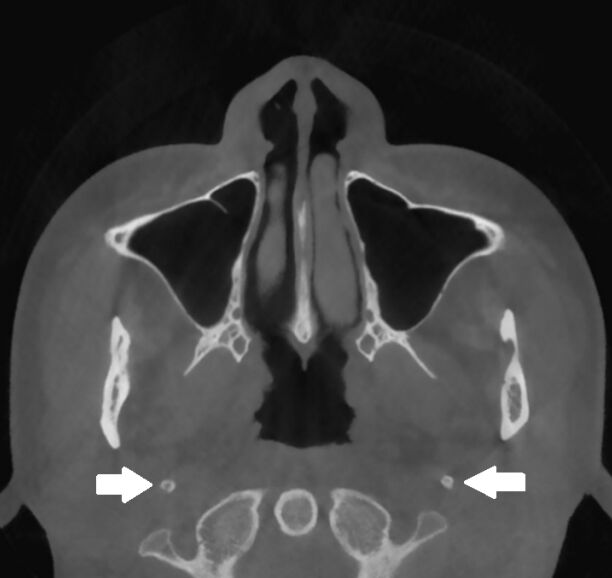

66.17歲男孩因上顎右側有一個無疼痛的腫脹而來求診,經X光檢查(如附圖)發現一個放射線不透過性影像如 箭頭所示之區域,根尖片可見到此病變與周圍界線不清楚,此病患最可能罹患下列何種疾病? (A)家族性巨大畸形牙骨質瘤(familial gigantiform cementoma)(B)繁盛性牙骨質骨發育不良(florid cemento-osseous dysplasia)(C)纖維性發育不良(fibrous dysplasia)(D)骨化纖維瘤(ossifying fibroma)